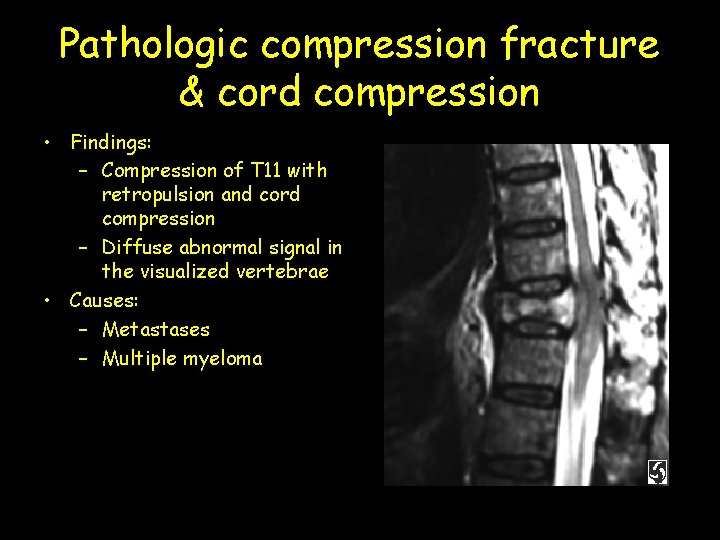

Pathologic compression fracture & cord compression • Findings: – Compression of T 11 with retropulsion and cord compression – Diffuse abnormal signal in the visualized vertebrae • Causes: – Metastases – Multiple myeloma